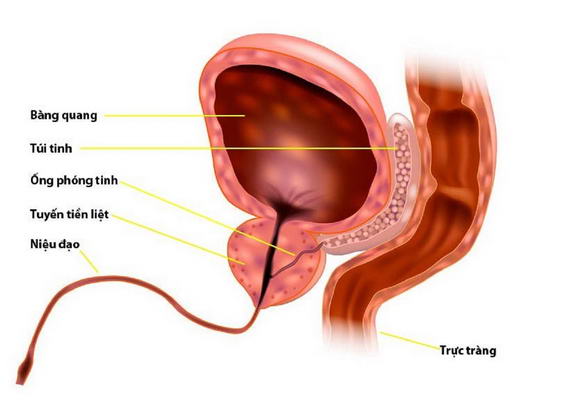

Sỏi tuyến tiền liệt là gì? – Phẫu thuật cắt bỏ tuyến tiền liệt bằng laser

Sỏi tuyến tiền liệt nằm trong các ống dẫn tuyến tiền liệt và cơ chế hình thành chưa rõ ràng. Tuy nhiên, có giả thuyết cho rằng do tắc nghẽn các ống dẫn tuyến tiền liệt xung quanh tuyến tiền liệt phì đại hoặc do viêm mạn tính sẽ gây ra sỏi tuyến tiền liệt nguyên phát, sỏi thứ phát được hình thành do sự trào ngược nước tiểu.

Tỷ lệ xuất hiện sỏi tuyến tiền liệt ở bệnh nhân phì đại hoặc viêm tuyến tiền liệt nhiều hơn ở người có tuyến tiền liệt bình thường. Sỏi tuyến tiền liệt thường xảy ra ở đàn ông trung niên và người già.

Ung thư tiền liệt tuyến có thể được phát hiện qua xét nghiệm PSA. Khi di căn, bệnh có thể gây ra đau xương và ảnh hưởng đến tủy sống, dẫn đến yếu chân hoặc không kiểm soát đại tiểu tiện. Những triệu chứng thường phát triển âm thầm, làm khó khăn trong việc phát hiện sớm. Phẫu thuật cắt bỏ tuyến tiền liệt bằng laser